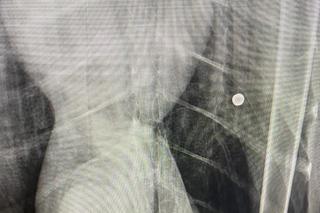

Łabędzica Lusia nie lata już bardzo długo, a świadczą o tym pióra w ogonie, które zmieniły kolor. Ptak bardzo cierpi. W swoim ciele ma śruty, które uszkodził mu skrzydło oraz dziób. Ktoś bezmyślnie strzelał do tego zwierzęcia.

Lusia trafiła do Fundacji Ada w Przemyślu, gdzie weterynarze natychmiast udzielili jej pomocy i od razu zdiagnozowali problem. Do ptaka ktoś strzelał z wiatrówki. Zadał łabędzicy  ból i skazał ją na cierpienie dla zabawy! Zwierzę ma uszkodzony dziób i staw w skrzydle, przez co nie może latać, a kości bez pomocy weterynarzy nie zrosną się. Lusia zostanie w Lecznicy póki nie wyzdrowieje.